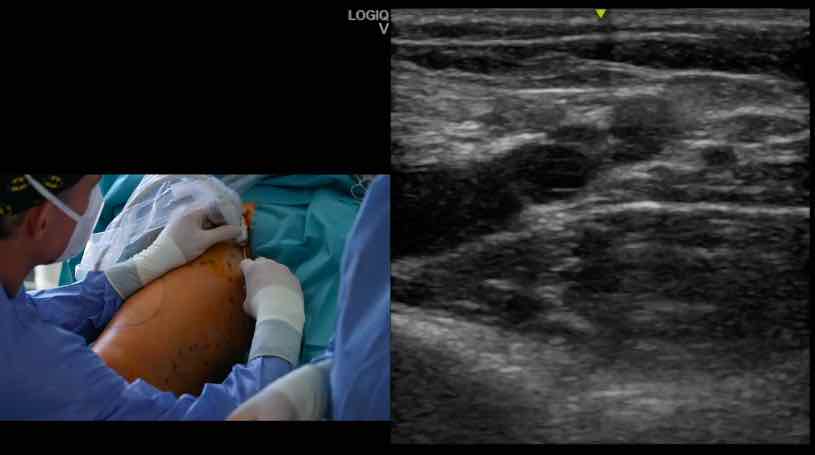

15. Freiburger Venen-Workshop – thumbnail 1 of 8 15. Freiburger Venen-Workshop – thumbnail 2 of 8 15. Freiburger Venen-Workshop – thumbnail 3 of 8 15. Freiburger Venen-Workshop – thumbnail 4 of 8 15. Freiburger Venen-Workshop – thumbnail 5 of 8 15. Freiburger Venen-Workshop – thumbnail 6 of 8 15. Freiburger Venen-Workshop – thumbnail 7 of 8 15. Freiburger Venen-Workshop – thumbnail 8 of 8

15. Freiburger Venen-Workshop

Live-Operationen - Endovenöse Technik sinnvoll einsetzen